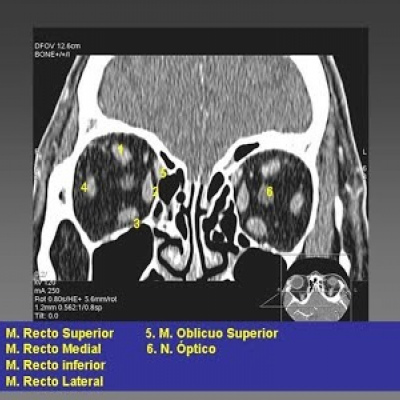

Tomografia computada de orbitas. EN. Codigo CUPS 879121 (2022)